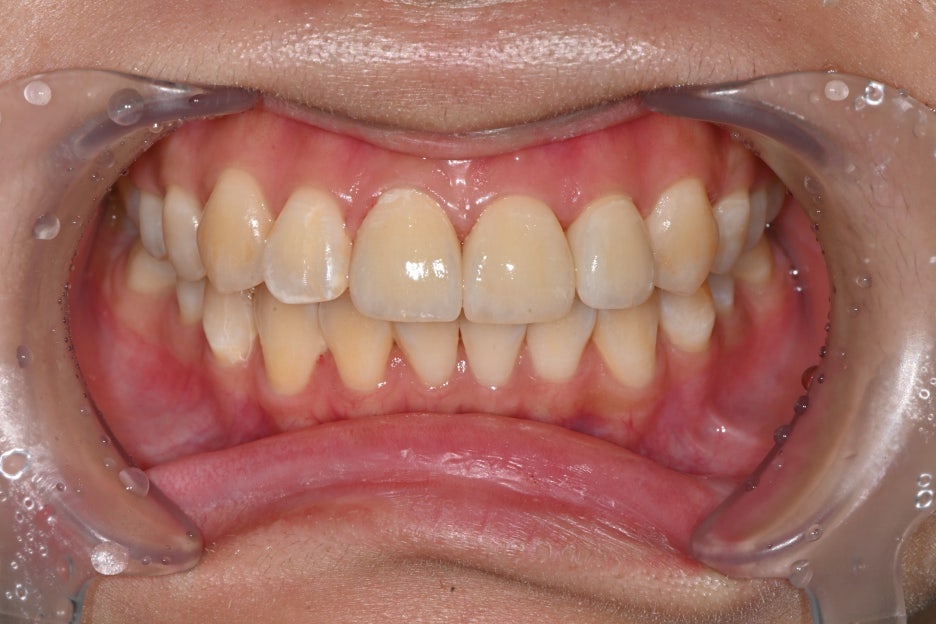

치료 전 후 사진

치료전, 치료후 사진

치료 후 환자분은

“앞니가 다시 가지런해져서 웃을 때

자신감이 생겼다”

며 만족감을 표현하셨습니다.

또한 주변 지인들이 자연스럽다고 말해주어

더욱 안심하셨습니다.